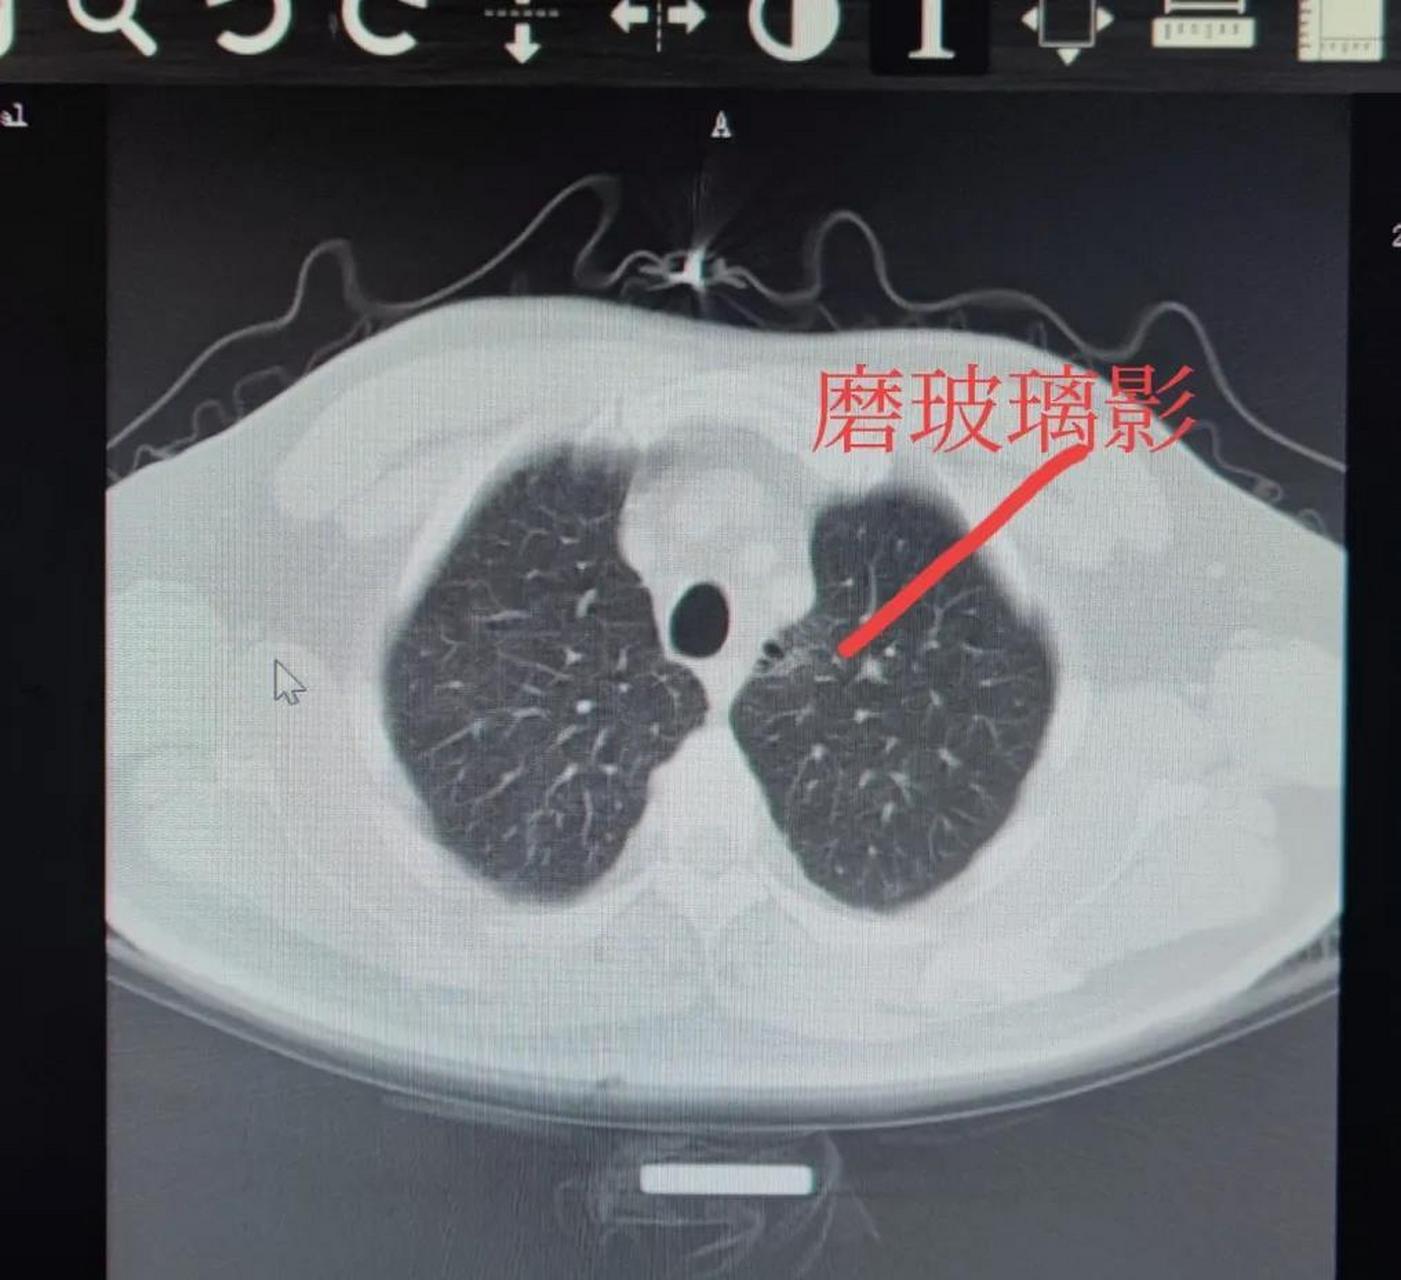

烟龄40多年,每天不到一包,不咳不喘,极轻度的慢支肺气肿患者的肺ct#给

图片尺寸1610x1280